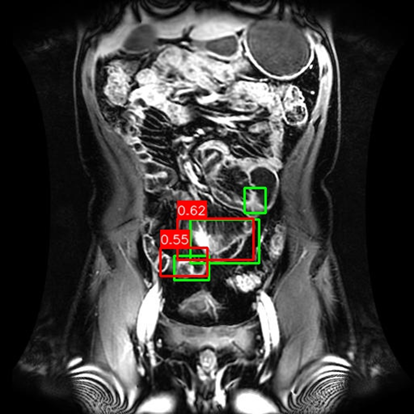

(a) Mask R-CNN [He2017MaskRCNN]

(b) DiffusionDet [Chen2023DiffusionDet_ICCV]

(c) DeFloMat (Ours)

Figure 3: Qualitative Comparison on Crohn’s Disease MRE Test Set. The figure compares detection results from (a) Mask R-CNN, (b) DiffusionDet (S=3S=3), and (c) DeFloMat (Ours, S=3S=3) on challenging MRE slices. Green boxes indicate True Positives (TP, IoU 0.1\geq 0.1), Red boxes indicate False Positives (FP), and Purple boxes indicate False Negatives (FN). DeFloMat consistently demonstrates superior localization quality and sensitivity: it successfully detects subtle inflammation regions (TP) that are often missed (FN, Purple boxes) by the Mask R-CNN baseline (Row 2, 4). Furthermore, DeFloMat provides tighter bounding box localization compared to DiffusionDet, confirming the benefit of learning the direct, deterministic flow field. The results show DeFloMat’s robustness in capturing varying sizes and numbers of inflammatory lesions.

Qualitative Assessment.

Figure 3 provides visual evidence of the models’ performance on challenging MRE slices, where inflammatory lesions can be subtle or obscured. The qualitative results underscore DeFloMat’s enhanced localization fidelity. In challenging cases (e.g., Row 2 and 4), Mask R-CNN and DiffusionDet frequently produce False Negatives (FN, Purple boxes), failing to detect clear inflammation sites. In contrast, DeFloMat reliably converts these FNs into True Positives (TP, Green boxes) by providing tighter and more accurate bounding box predictions. This suggests that the deterministic velocity field learned via Flow Matching is highly effective at precisely directing the proposal centers towards the true lesion locations, a characteristic that is vital for accurate clinical reporting. DeFloMat’s ability to achieve such precise localization with only S=3S=3 steps highlights its clinical utility for rapid diagnostic auxiliary systems.